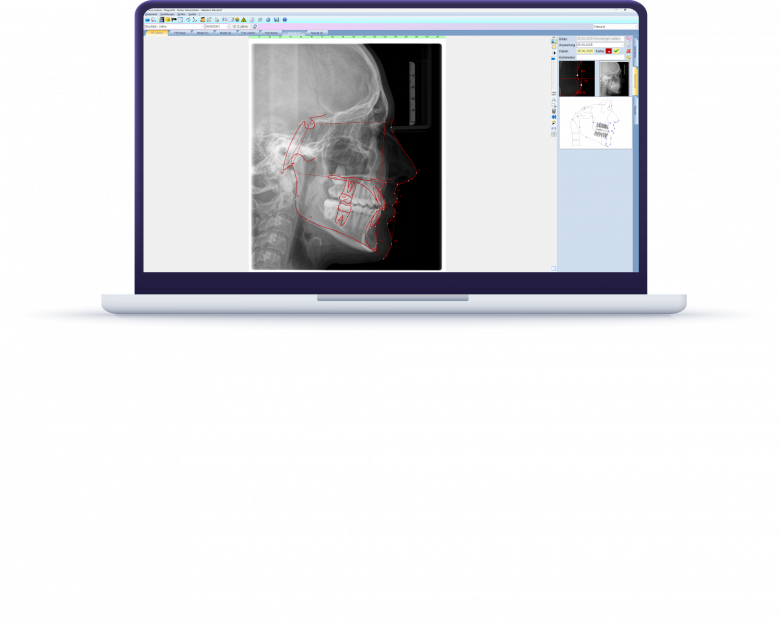

Ob Röntgen-, Foto- oder 3D-Aufnahmen – mit ivoris® analyze erfolgt die digitale Bildanalyse direkt aus der Patientenakte. Vielfältige Darstellungs- und Präsentationsmodi erleichtern die Befundung und machen Ergebnisse für Patient:innen transparent und nachvollziehbar. Mehr als 100 Analysevorlagen bieten Ihnen jederzeit die passende Grundlage für eine präzise Behandlungsplanung.

Mit der Fernröntgen-Analyse in der digitalen Kieferorthopädie behalten Sie Wachstumsverläufe und Behandlungsfortschritte jederzeit präzise im Blick.

- grafische Überlagerung von Durchzeichnungen in beliebigen Ebenen

- tabellarische Gegenüberstellung von Anfangs-, Zwischen- und Endbefund sowie Überlagerung von Bild und Tracing

- Analysevorlagen nach Bergen, Bjork, Hasund, Jarabak, McNamara, McGann, Rakosi, Ricketts, Sampermans, Segner, Steiner, Sato, Slavicek, Tweed, Wingberg u. v. m.